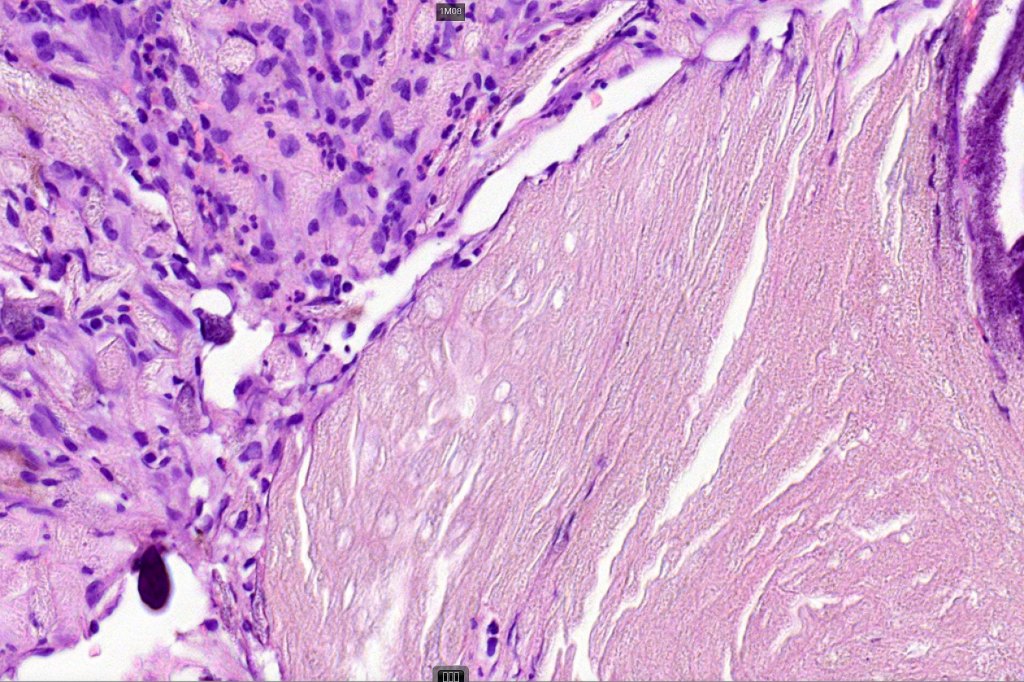

•Basophilic small cells which transition towards supramatricial (orange staining) and ultimately ghost cells with intensely eosinophilic cytoplasm

•Late features include calcification and bone formation

•Foreign body reaction